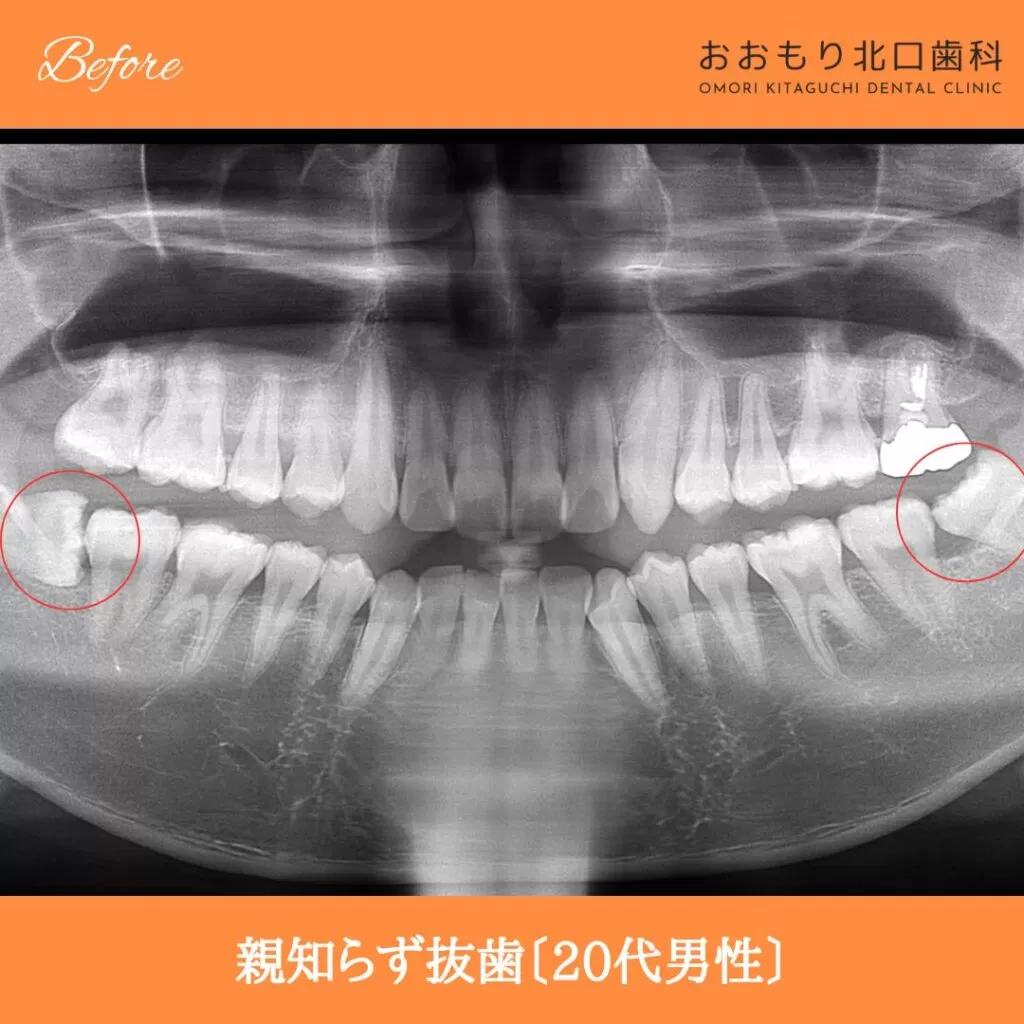

症例紹介㊷親知らず抜歯(20代男性)

本日は「親知らず抜歯」を行われた患者さまのビフォーアフターをご紹介します。

【治療名】親知らず抜歯

【患者さん】20代男性

【費用(税込)】保険治療

【リスク】 親知らずの抜歯は、手術中は麻酔により痛みを感じることがほとんどありません。

しかし、麻酔が切れた後には、時には腫れや痛みが発生することがあります。